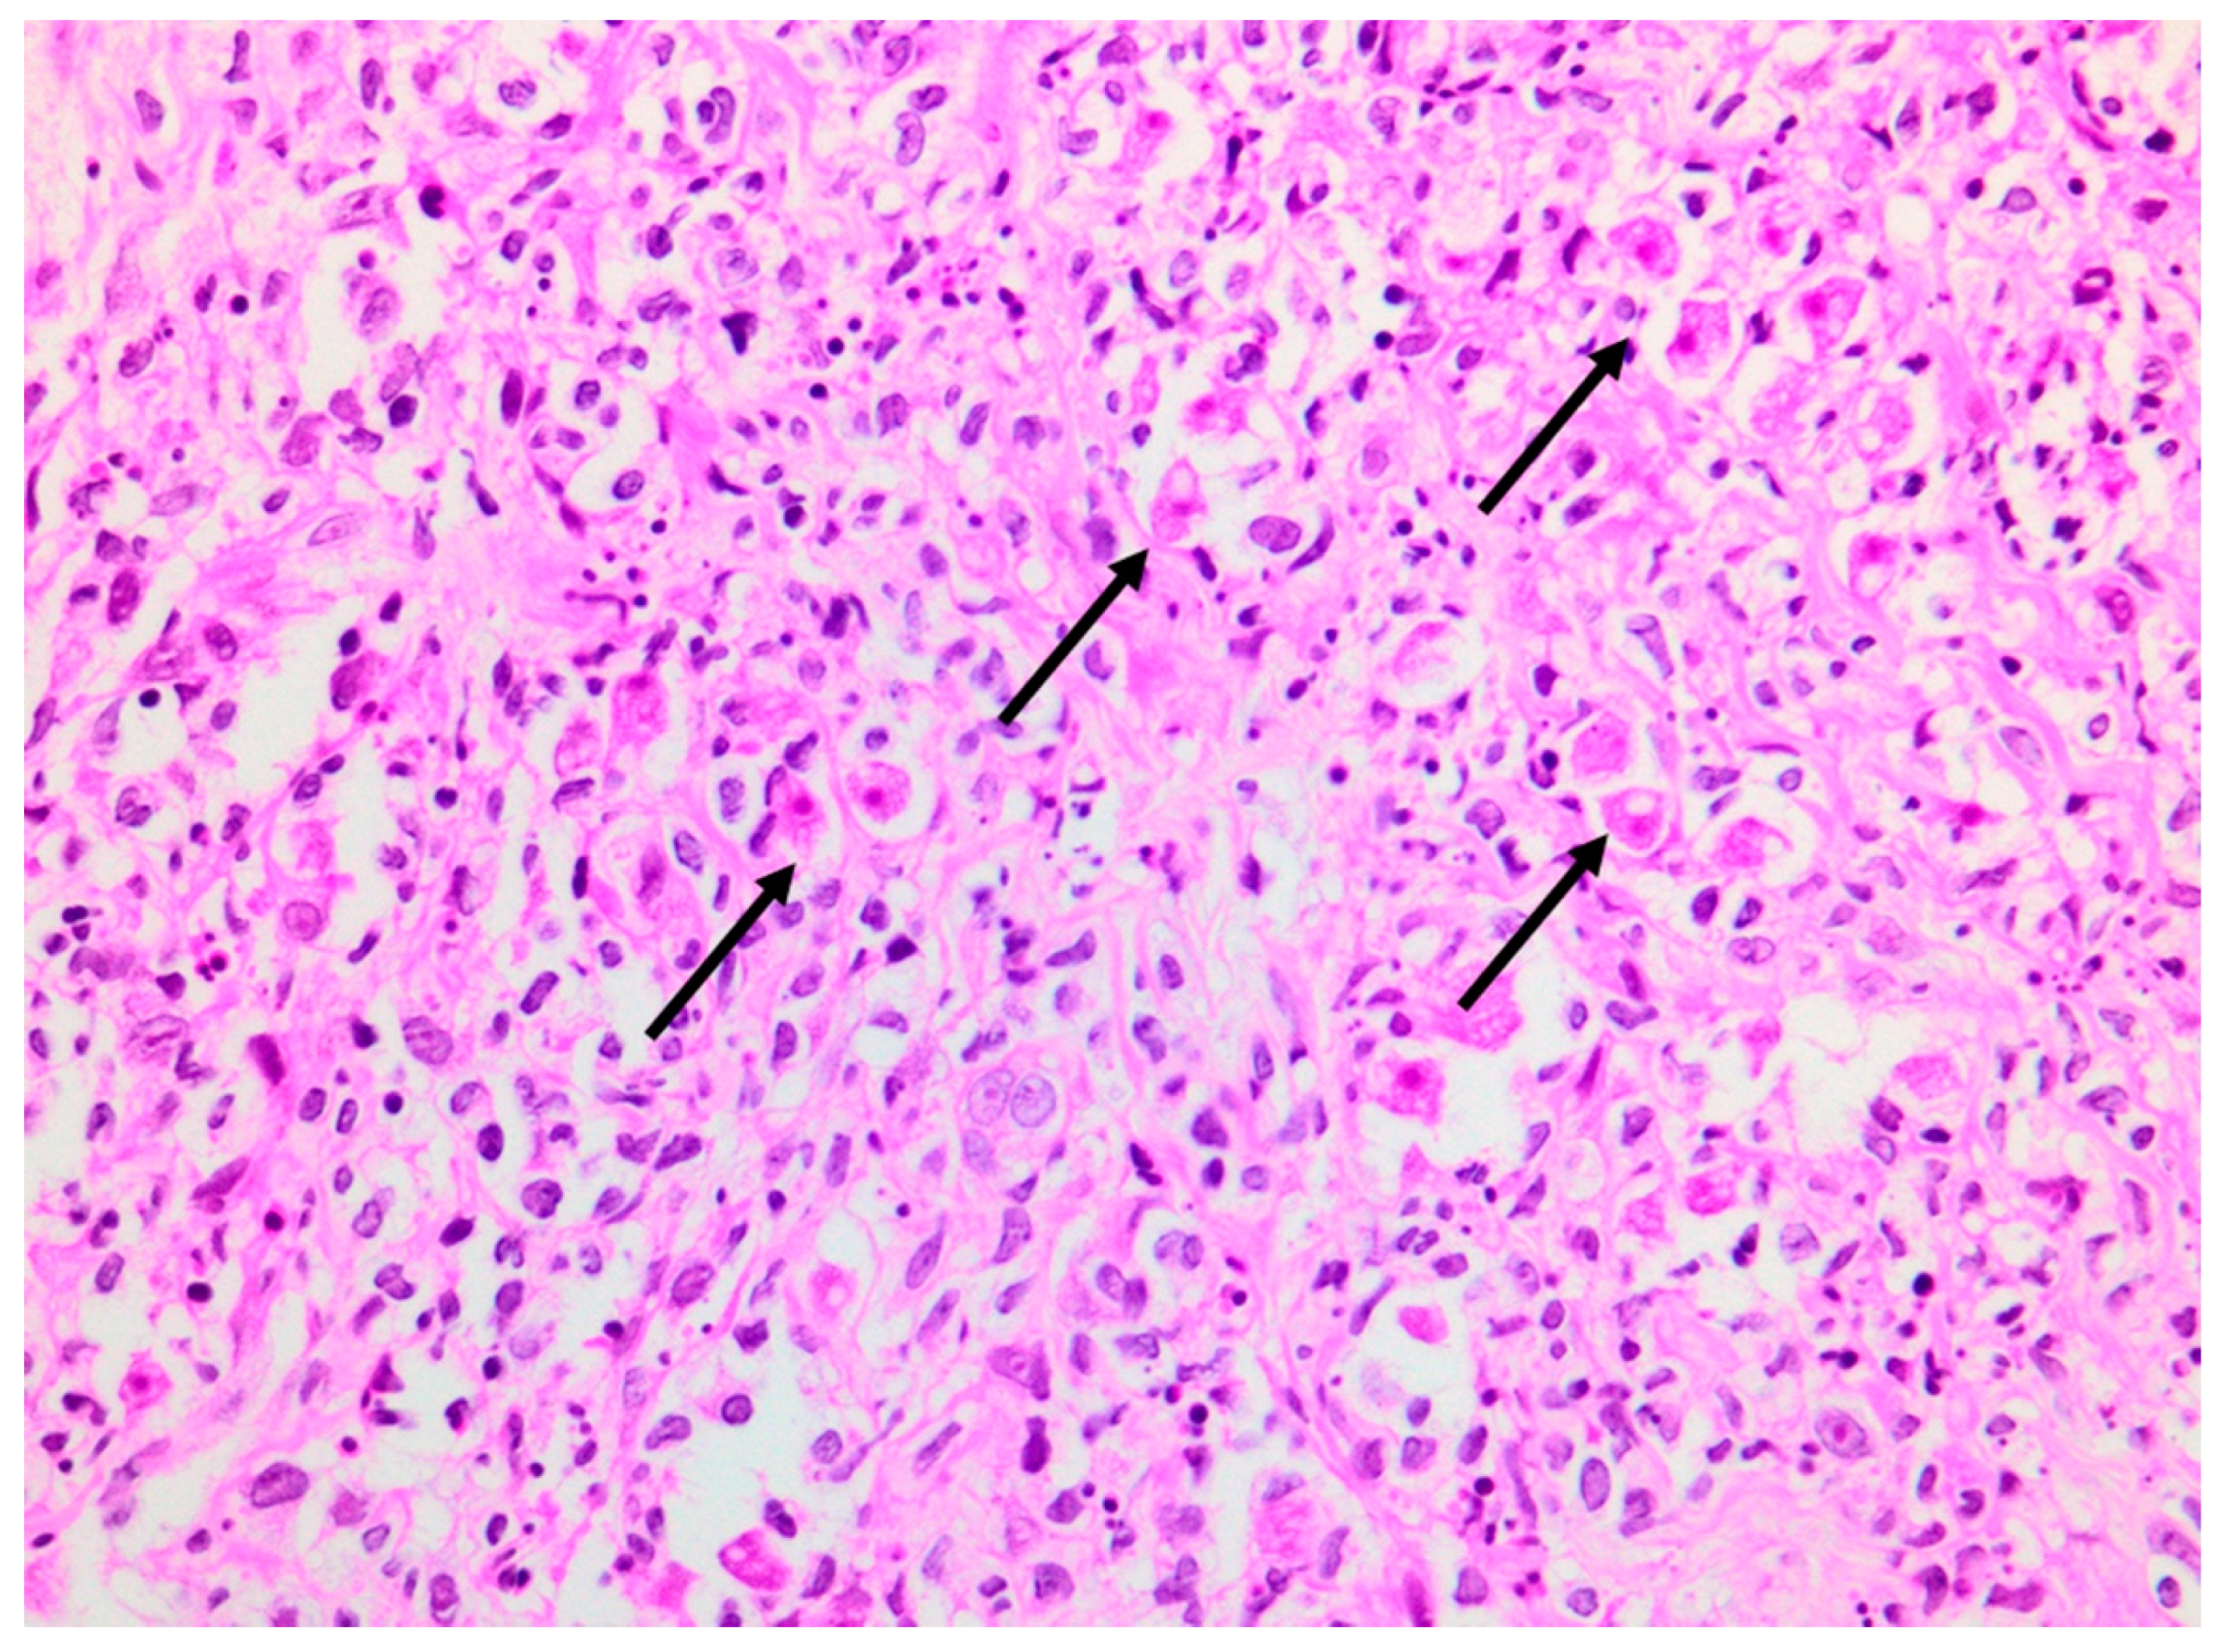

A deep skin punch biopsy was obtained from one of the lesions on the forearm, and submitted in 10% buffered formalin. The haematoxylin and eosin-stained sections revealed a polymorphous nodular deep dermal and subcutaneous inflammatory cell infiltrate comprising neutrophils, histiocytes, lymphocytes and eosinophils in response to conspicuous numbers of free-living amoebic organisms (Figure 5). Each round trophozoite was seen to possess a characteristic targetoid eosinophilic nucleus (Figure 6). Only rare, encysted forms were noted in the inflamed areas. Occasional subcutaneous vessels showed vasculitis. Erythrophagocytosis was conspicuously absent. There was no preponderance of histiocytic giant cells. The periodic acid-Schiff (PAS) stain was positive in some of the organisms, but the Grocott methenamine silver, TriPAS and Ziehl-Neelsen stains were negative. A diagnosis of cutaneous acanthamoebiasis was rendered, and the infectious diseases service was consulted. Further skin biopsies were sent to the national reference parasitology laboratory at the National Institute for Communicable Diseases (NICD). Cultures and PCR testing of the isolate performed at the NICD according to published methods [8,9] confirmed the presence of an Acanthamoeba species, with further 18s rRNA gene-sequencing identifying the isolate as a T4 strain, Acanthamoeba polyphaga (>99% identity with GenBank sequence accession no. MN153018.1).

Figure 6. Acanthamoeba organisms (arrows), as seen under oil immersion. Note the characteristic targetoid appearance of the nuclei (haematoxylin and eosin, ×1000).